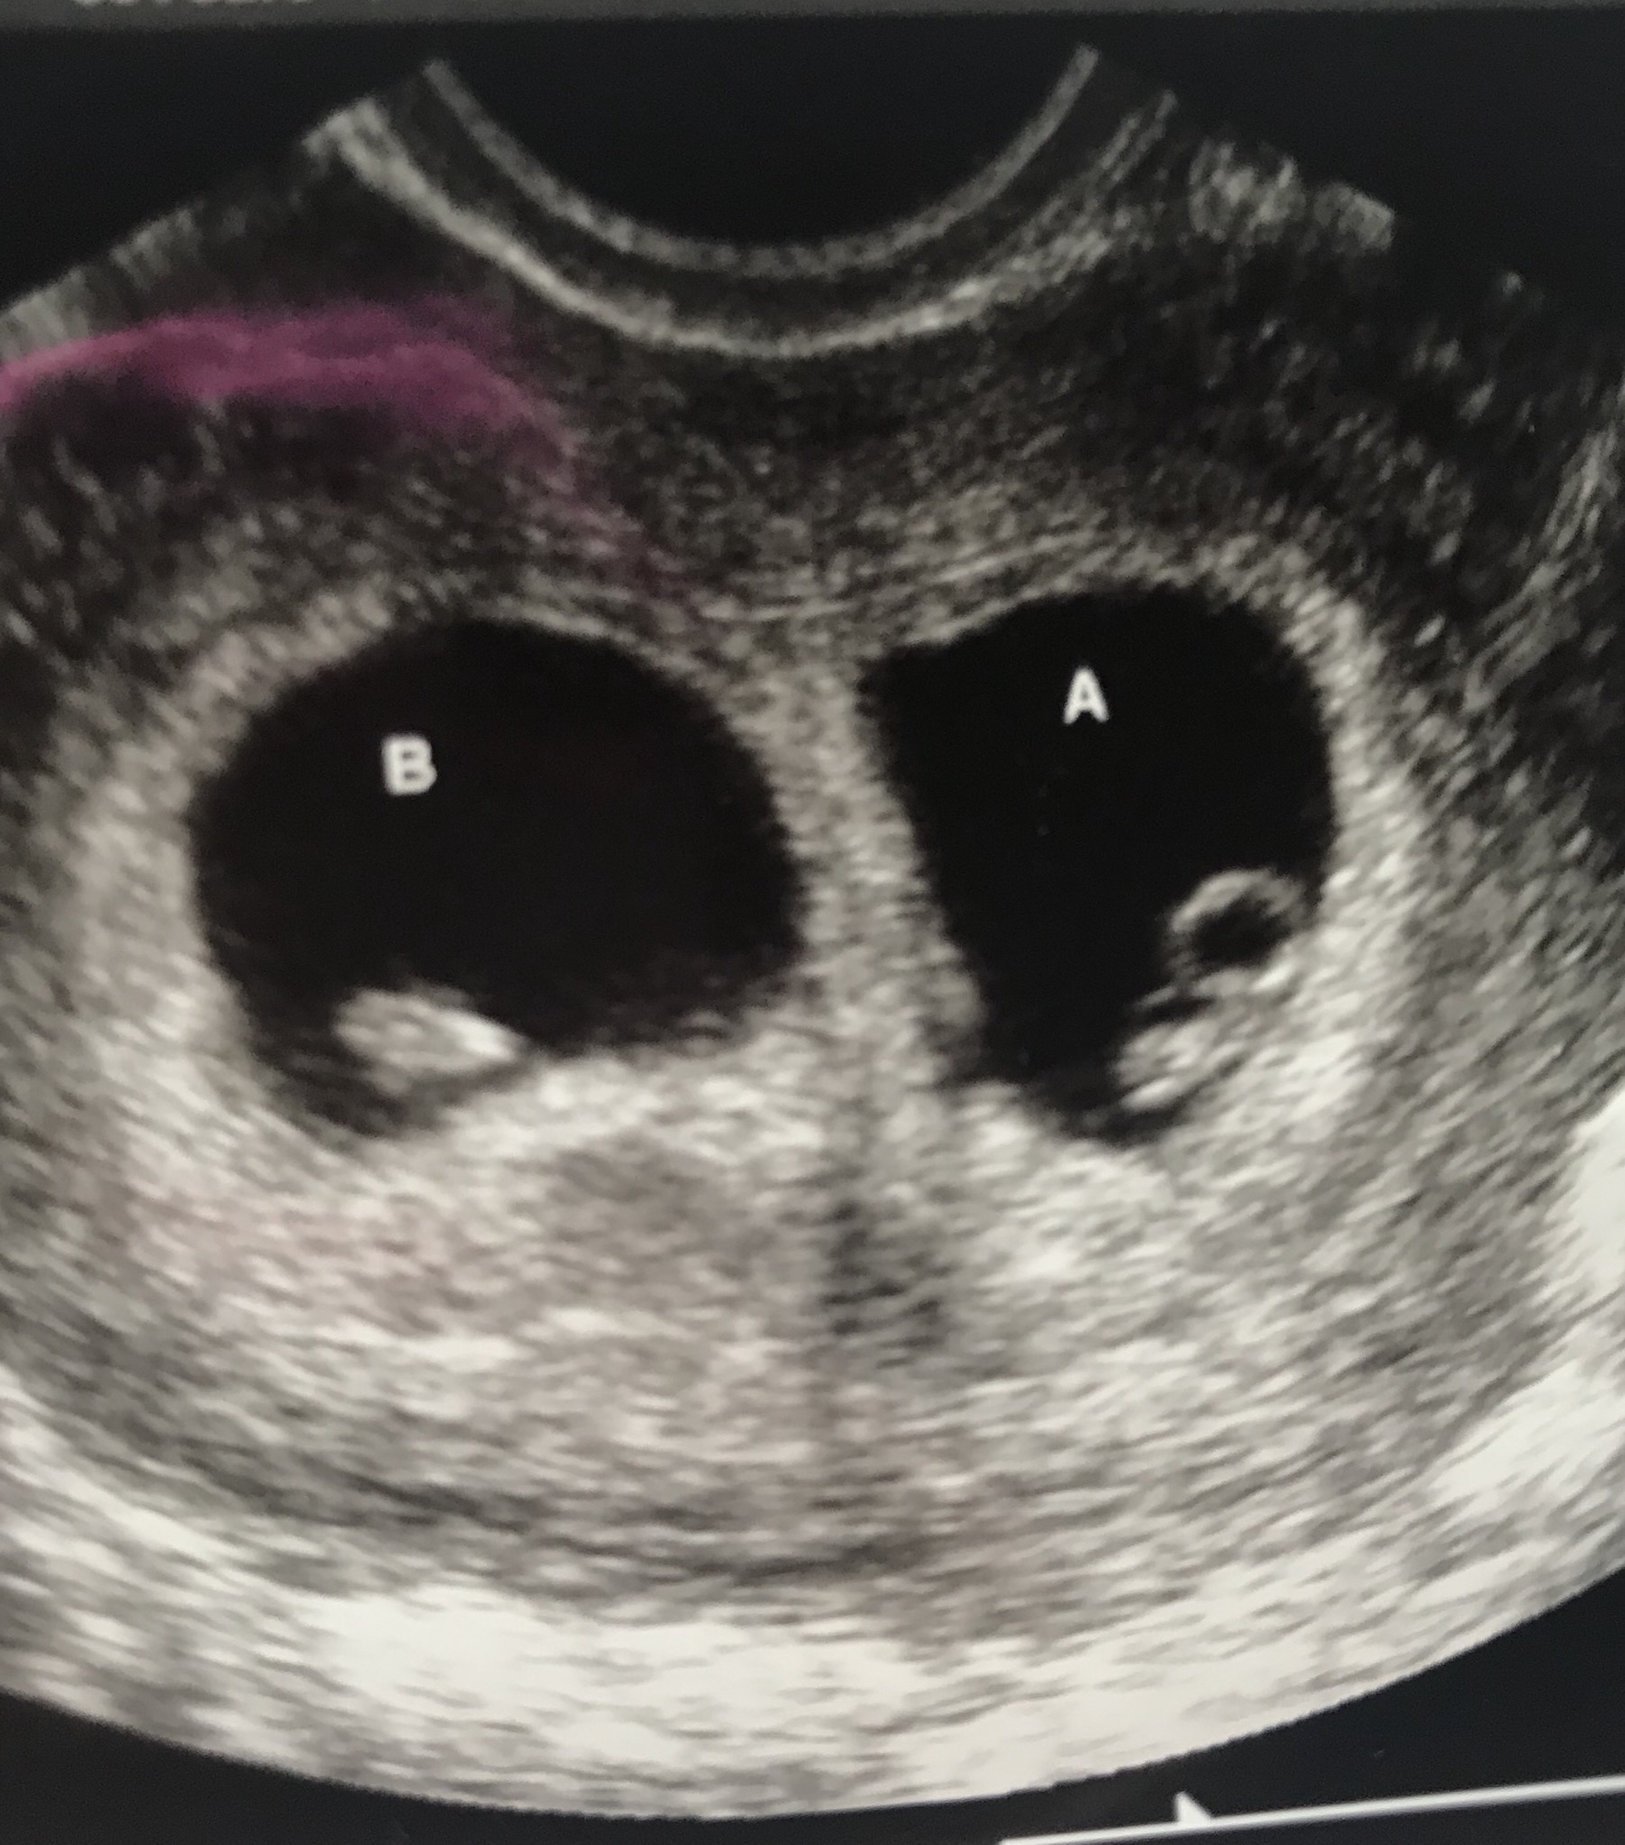

(Taken from June 2019)

Found out yesterday, I am having twins.. EDD 12.7.19

7w0d heartbeat 120